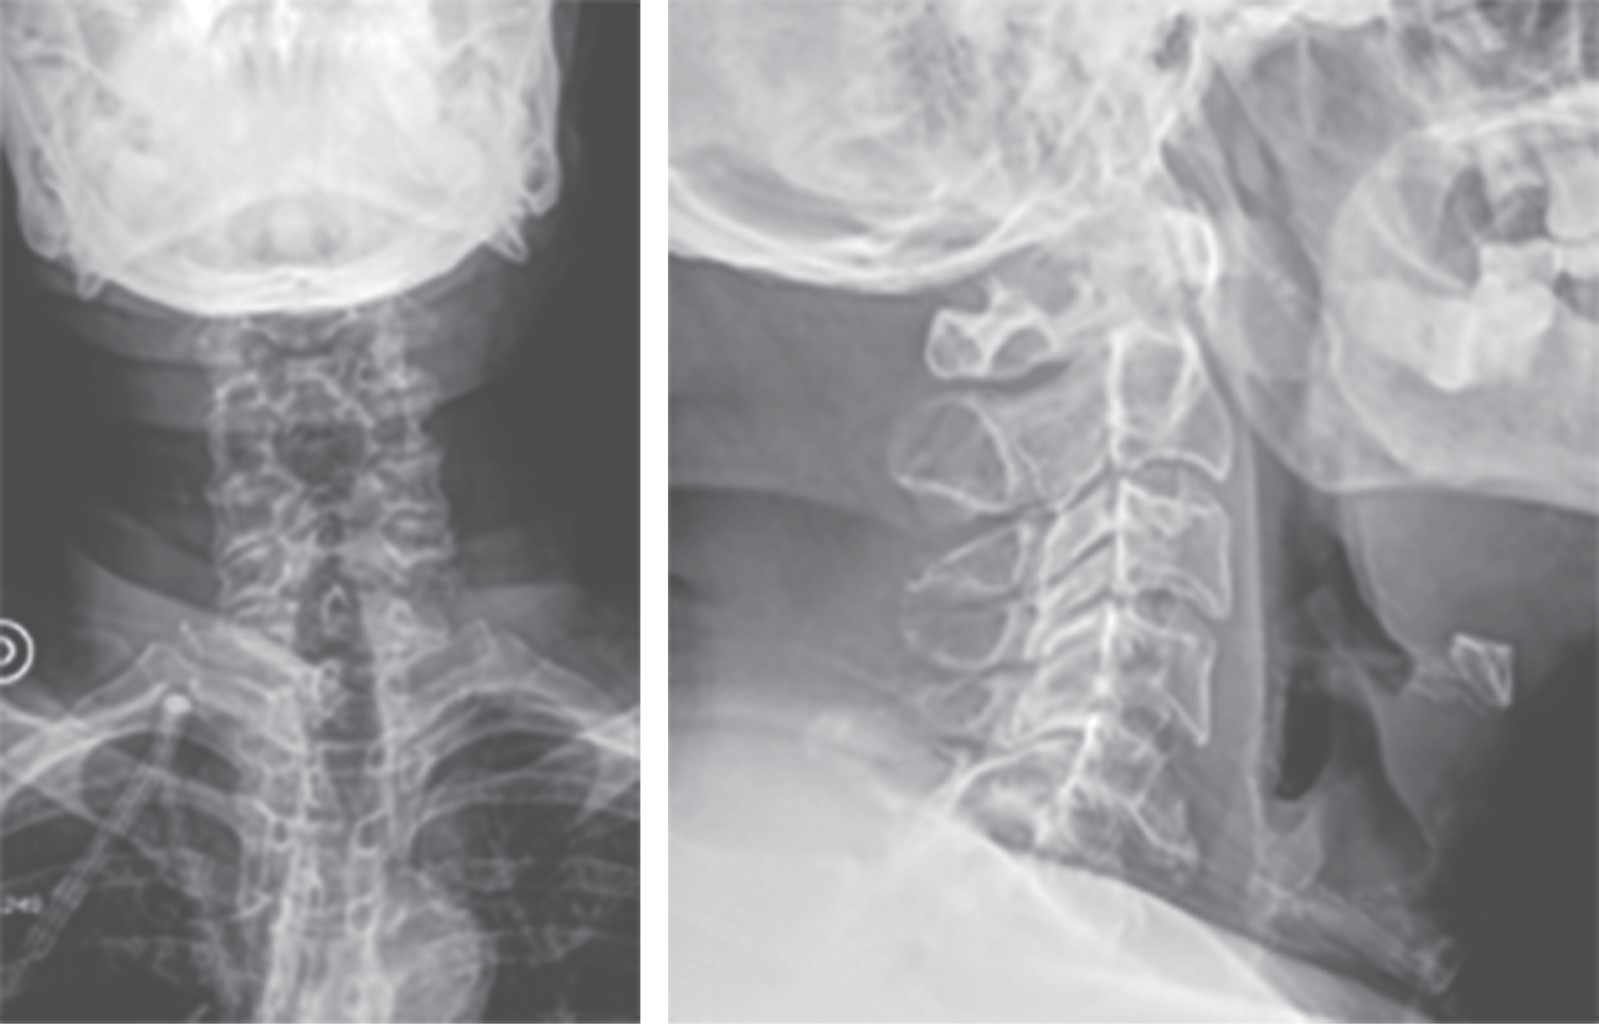

Figure 1

Figure 2